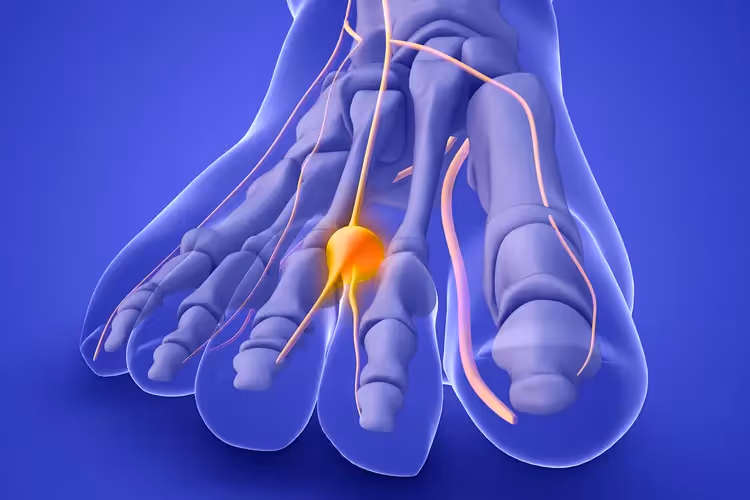

El Neuroma de Morton, también conocido como síndrome de Morton o neuroma interdigital, es un engrosamiento benigno del tejido que rodea uno de los nervios que van hacia los dedos del pie. Contrariamente a lo que su nombre sugiere, técnicamente no es un neuroma verdadero (tumor nervioso), sino más bien una fibrosis perineural o engrosamiento del nervio debido a la compresión crónica.

Esta condición se desarrolla cuando el nervio interdigital plantar se comprime repetidamente entre los huesos metatarsianos, generando una respuesta inflamatoria que provoca el engrosamiento del tejido nervioso y, consecuentemente, los síntomas dolorosos característicos.

Anatomía del Pie: Entendiendo la Zona Afectada

Para comprender mejor esta patología, es fundamental conocer la anatomía del pie. Los nervios interdigitales plantares son pequeños nervios que se extienden desde el pie hacia los dedos, pasando por los espacios entre los huesos metatarsianos.

El Neuroma de Morton se localiza en el tercer espacio, siendo esta localización más frecuente aunque también hay otras:

- Tercer espacio interdigital (85% de los casos): Entre el tercer y cuarto dedo del pie (Neuroma de Morton)

- Segundo espacio interdigital (15% de los casos): Entre el segundo y tercer dedo del pie (Neuroma de Hauser)

- Raramente: En el primer o cuarto espacio interdigital (Neuroma de Joplin, Heuter e Iselin)